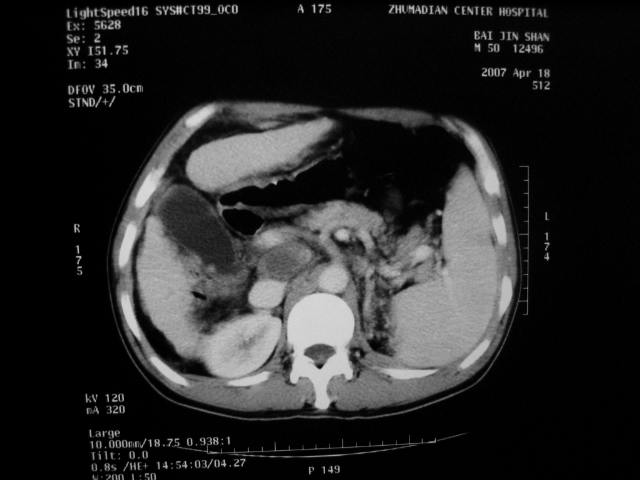

标题: CT7751:病人,50岁,肝硬化多年,行CT三期扫描 [打印本页]

标题: CT7751:病人,50岁,肝硬化多年,行CT三期扫描

肝硬化 脾大 胃底静脉曲张 肝癌 门腔间淋巴结肿大

肝癌、肝硬化、脾大、门静脉高压、胃底静脉曲张.

肝硬化、脾大,静脉曲张,肝右叶低密度灶,增强无明显强化,还是考虑肝癌可能性大,建议结合afp检查。

考虑肝硬化,脾大,静脉曲张,肝右叶低密度灶,右肝癌可能性大。